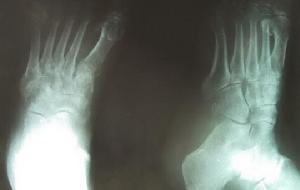

3、骨X线摄影:可发现骨萎缩像。 医学百科网 | YxBaike.Com